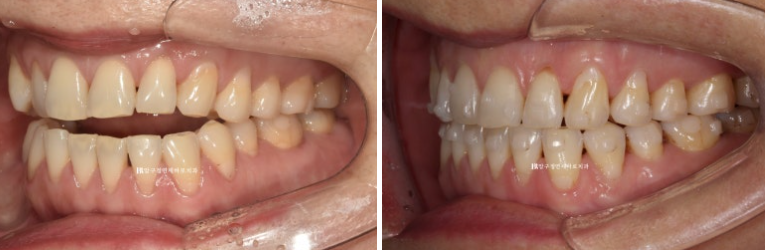

23.05~23.12

첫번째 작은어금니까지 8개 치아는 떠있고 두번째 작은어금니부터 큰어금니까지 3개씩 닿아있는 상태입니다.

이런 상태에서는 닿고있는 위 어금니 3개씩 총 6개 치아를 함입시키는 치료계획으로 진행합니다.